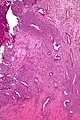

| Micrograph of a uterine adenosarcoma showing a mitotically active malignant stroma and benign glands. H&E stain. | |

Uterine adenosarcoma have, by definition, a malignant stroma and benign glandular elements. The World Health Organization (WHO) criteria have a mitotic rate cut point; however, this is often disregarded, as bland-appearing tumours with a low mitotic rate are known to metastasize occasionally.[2]